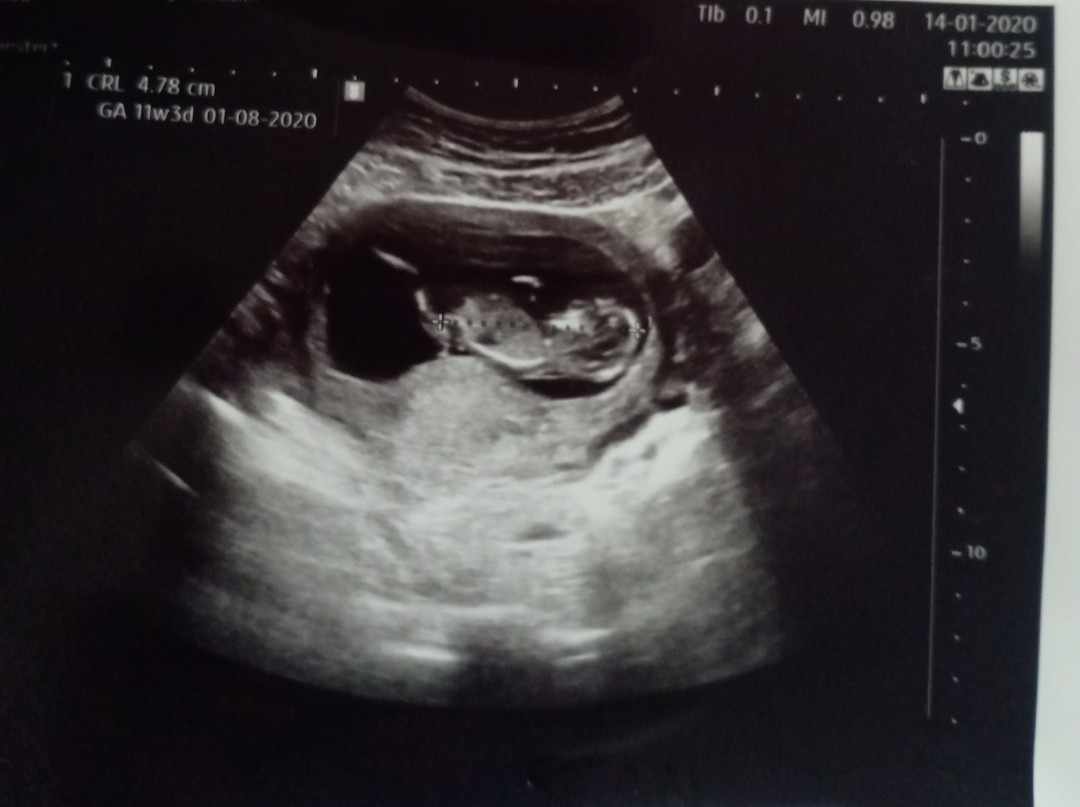

5 ก.ค ผู้กญิงจร้าา

4 ก.ค ผู้หญิงค่ะ😄